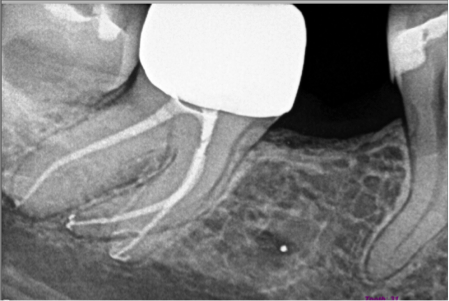

Dr. Howard and Dr. Camba use state-of-the-art technology including an operating microscopes with assistant side binoculars, digital imaging, ultrasonic instrumentation, fiber optics, and CBCT ‘Cone-Beam’ 3D technology to treat patients quickly and comfortably.